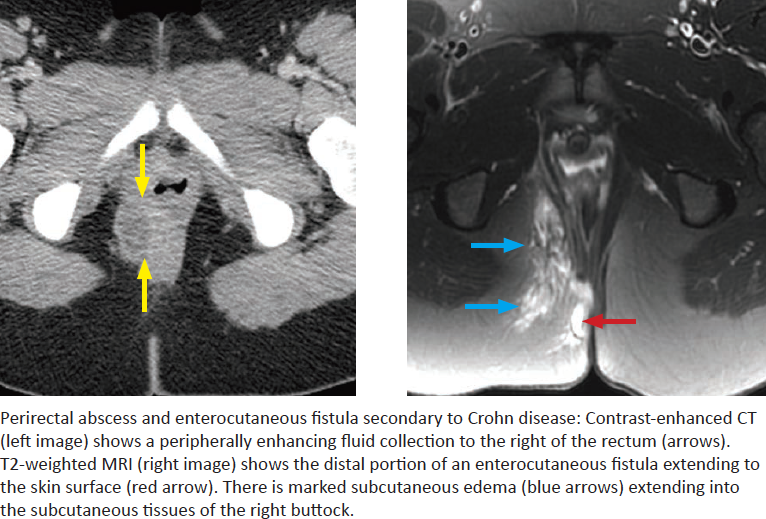

Crohn Disease

What are some complications of Crohn disease?